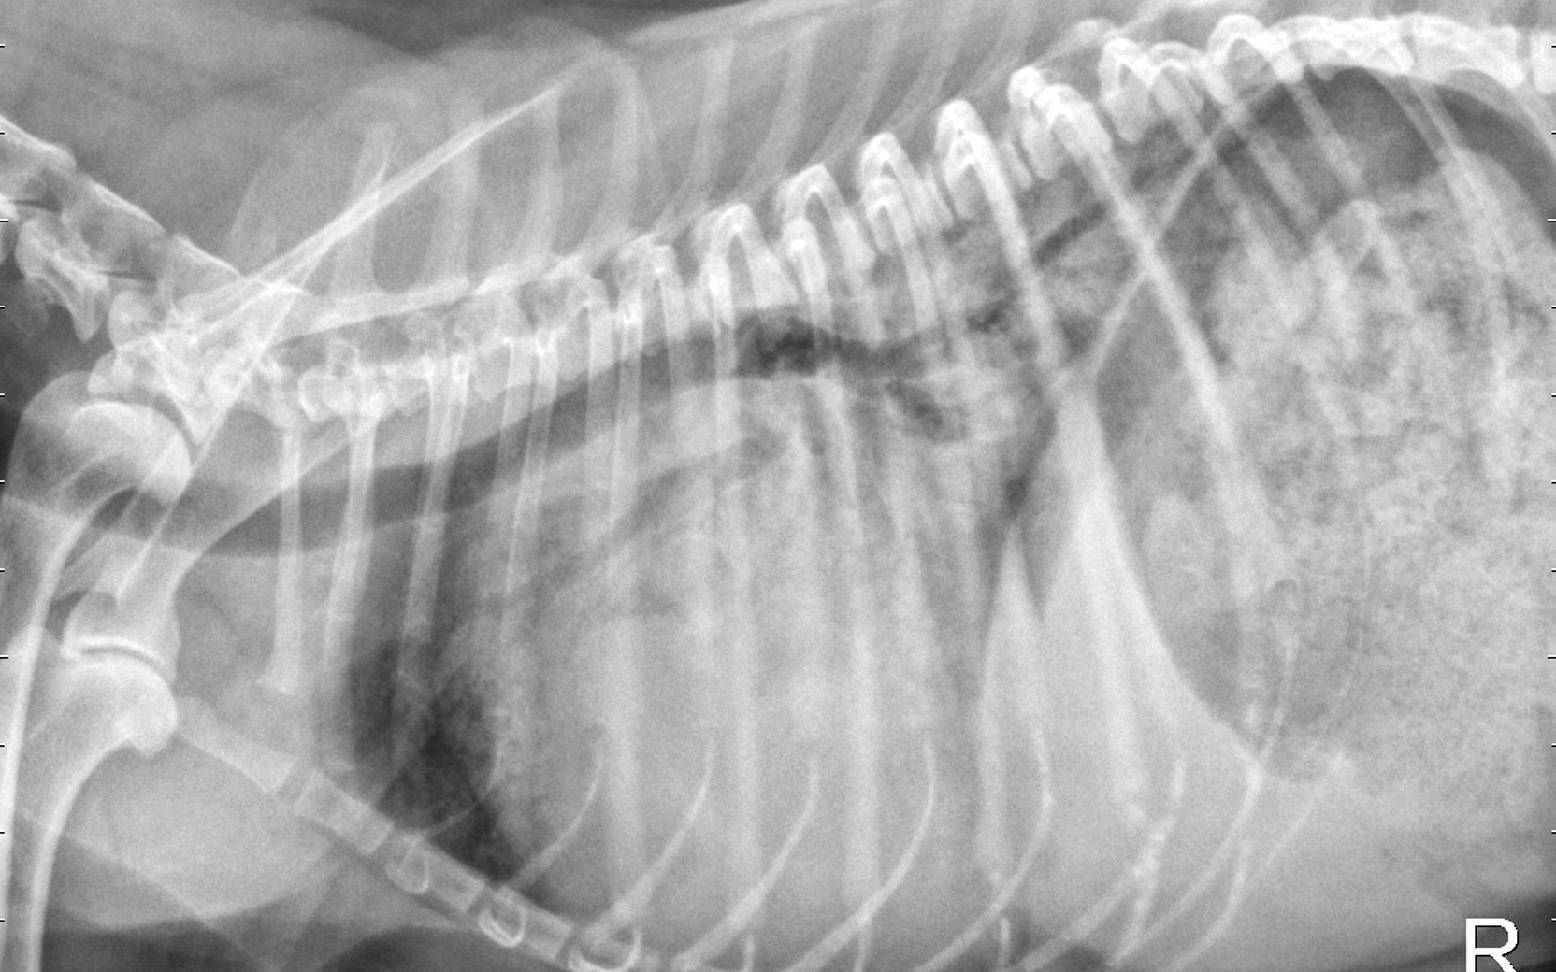

Das Abhören des Herzens und der Lunge liefert daraufhin die ersten konkreten Informationen über eine gestörte Herzfunktion. Weitere spezielle Untersuchungsmethoden, wie EKG (=Elektrokardiogramm), Ultraschall oder Röntgen (siehe entsprechende Artikel) dienen der Bestätigung und genauen Differenzierung der Diagnose.